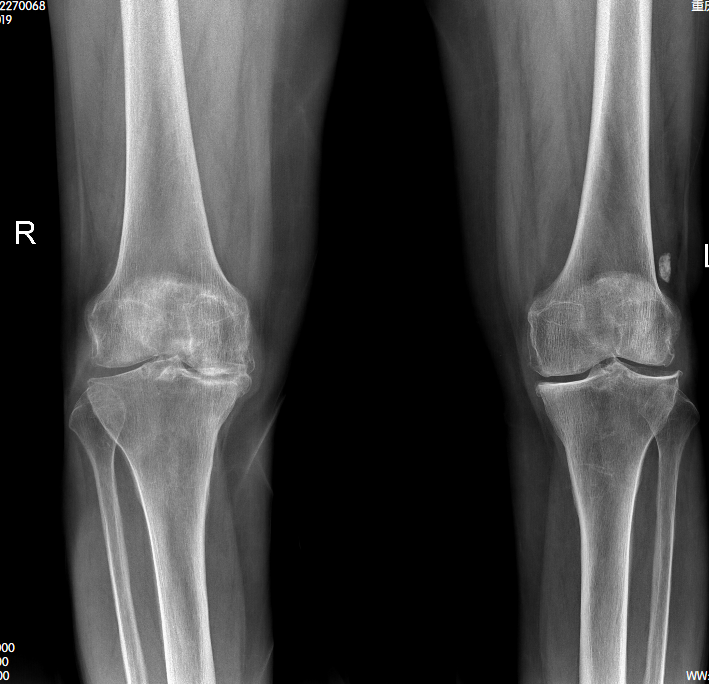

“十年前右边膝盖就开始疼,下地干活哪顾得上,吃片止痛药就扛过去了。”今年82岁的唐婆婆回忆道。随着岁月推移,近两年左侧膝关节也相继出现疼痛症状,长时间行走后便跛行明显,严重影响日常起居。在当地医院检查后,她被确诊为双膝关节骨性关节炎。因年事已高不愿折腾,唐婆婆先选择保守治疗,却始终未能缓解病痛。

为让母亲安享晚年,唐婆婆的儿子多方打听后,于去年2月底带她前往重庆长城骨科医院关节外科就诊。“考虑到患者年龄大,我们立即启动多学科会诊,量身定制手术方案。”关节外科主任詹学锋介绍,骨性关节炎是中老年常见退行性关节病,唐婆婆疼痛及跛行症状显著,保守治疗已无意义,具备明确手术指征。最终团队为其实施左膝关节置换手术,术后恢复效果远超预期。

詹学锋主任详解,骨性关节炎常累及负重关节,病理变化始于软骨,逐步侵犯软骨下骨板及滑膜等组织,表现为关节疼痛、变形及活动受限。治疗需根据病情分级干预,早期可通过理疗、药物等保守方式控制症状,晚期则需手术治疗。

“胫骨高位截骨术可延缓关节退变,但无法彻底解决病痛。”詹主任表示,唐婆婆病情需通过人工膝关节置换手术才能根治,该手术能彻底解除疼痛、恢复关节功能,从根源上提升生活质量。